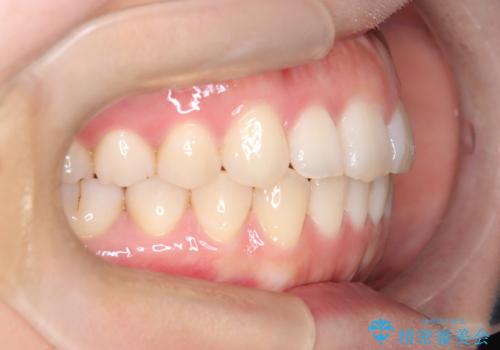

【インビザライン】前歯の凸凹を治したい

- 前歯の凸凹を主訴に来院されました。

インビザラインにて臼歯部の遠心移動を行いながら、できるだけ前歯が出ないように気を付けて治療を行っています。

遠心移動を行う必要があったので、患者様には顎間ゴムを使用していただきました。